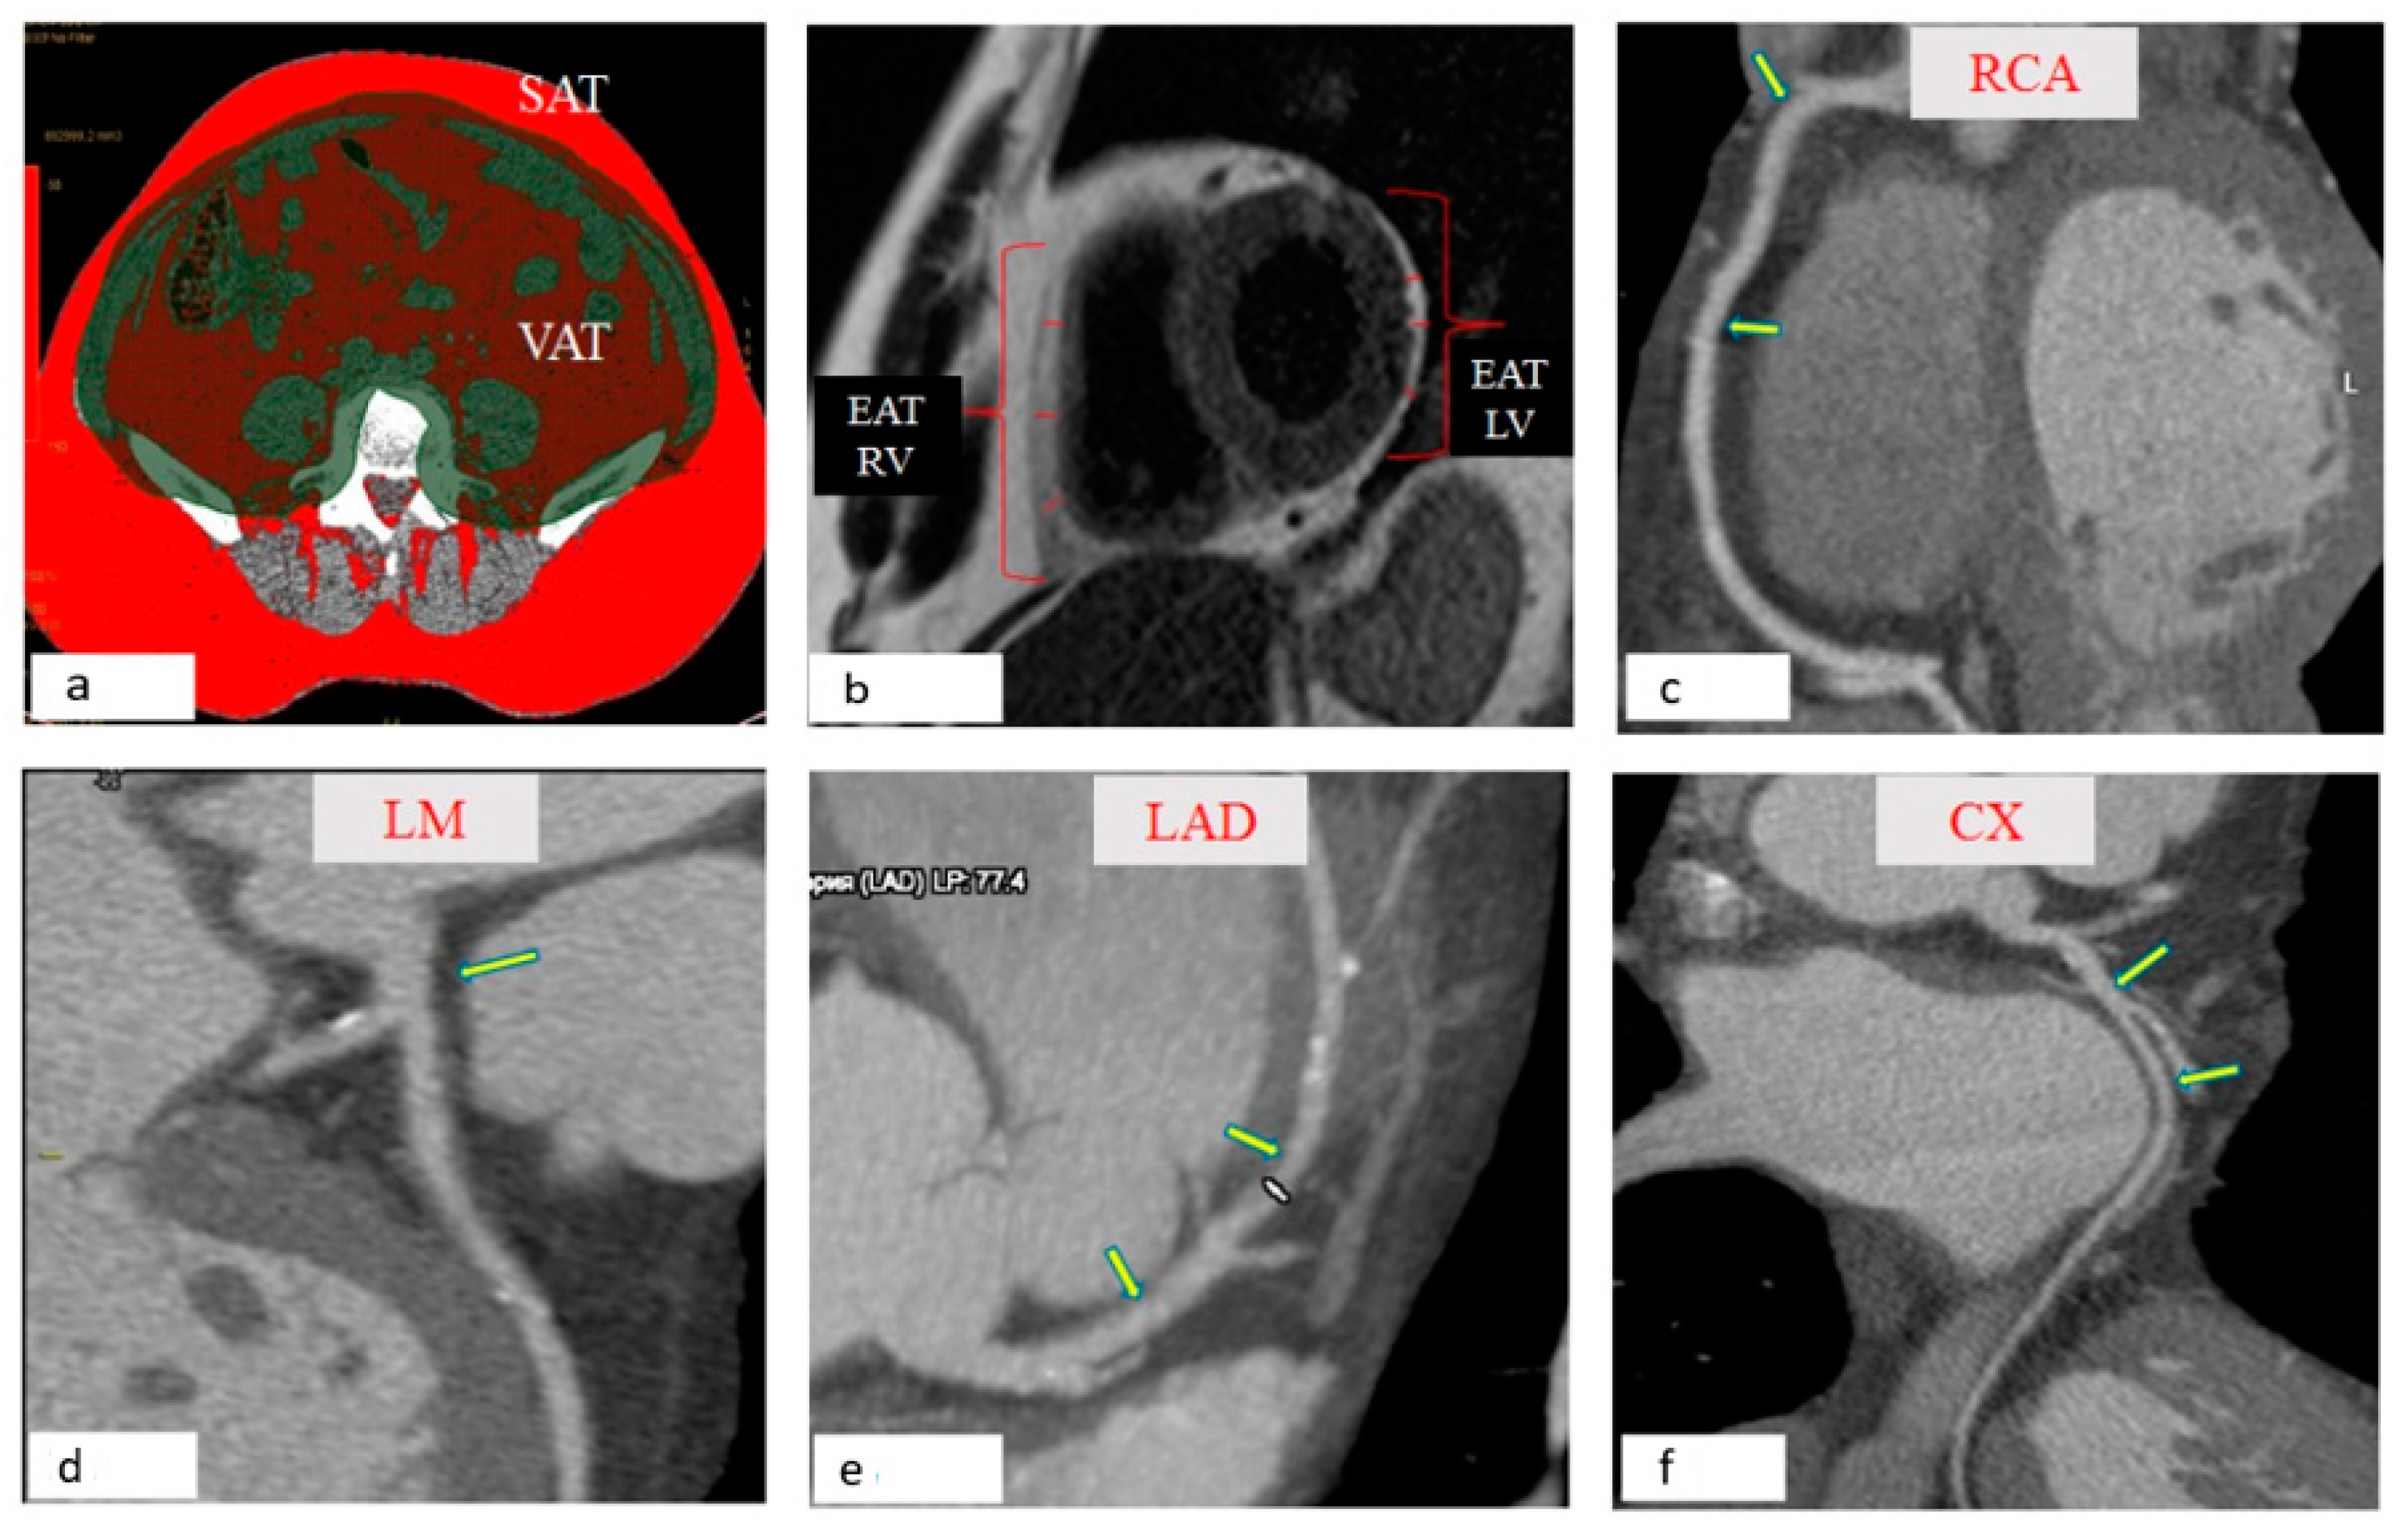

Jpm Free Full Text Relationship Between Epicardial And Coronary Adipose Tissue And The Expression Of Adiponectin Leptin And Interleukin 6 In Patients With Coronary Artery Disease Html